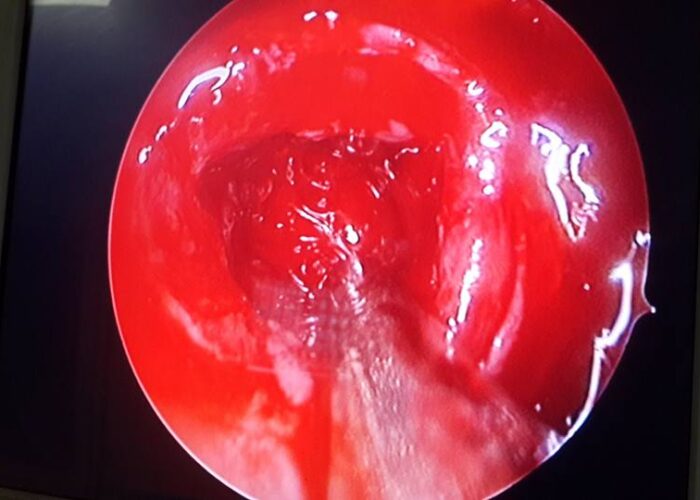

3 Endoscopic Pituitary Cases in Manik Hospital